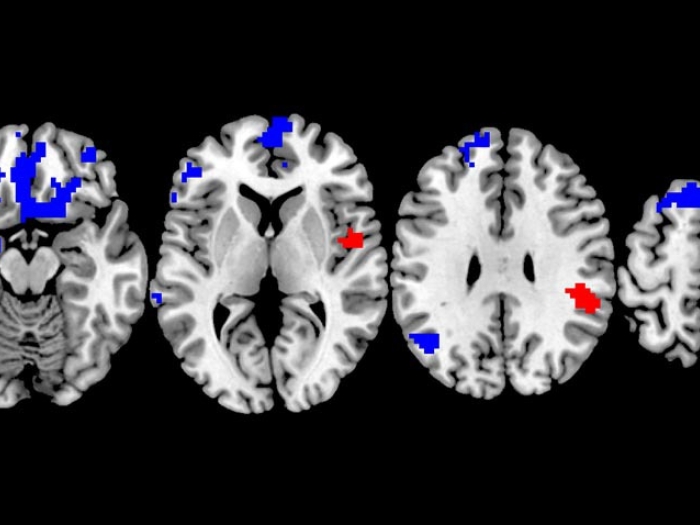

Brain scans of OCD.

Health Lab

Which OCD Treatment Works Best? New Brain Study Could Lead to More Personalized Choices

For people with OCD, or obsessive compulsive disorder, a new brain imaging study may help personalize treatment including exposure therapy.